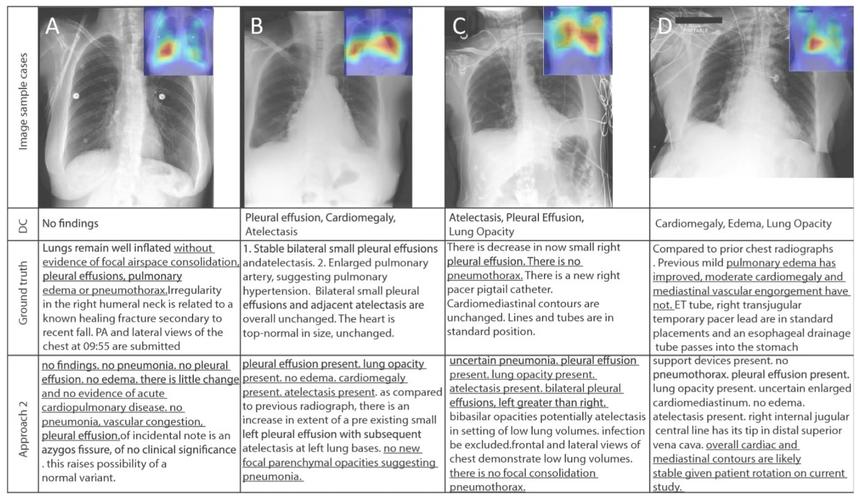

В первом ряду таблицы — рентгеновские снимки грудной клетки, во втором — диагноз врача коротко, в третьем — более развёрнутый комментарий врача, в четвёртом — описание, сгенерированное нейросетью. Подчёркнутые фрагменты демонстрируют, что версии искусственного интеллекта и врача в целом сходятся, хоть сам текст и нуждается в редактуре

Для обучения нейросети была создана большая база рентгеновских снимков и специальный радиологический словарь для повышения точности в использования радиологических терминов.